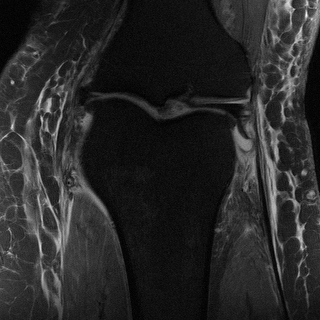

Edge preserving has always been a crucial concern in the design of reconstruction models. To improve the quality of reconstructed images and preserve image edges, some works suggested introducing edge priors in the original restoration problem to preserve image edges [4, 34]. However, they will suffer from complicated algorithm design and time-consuming training processes. Recently, some more efficient methods have been proposed to use edge maps as external guidance for image restoration. For example, Yang et al. [48] used off-the-shelf edge detectors to extract image edges from the degraded images. Fang et al. [12] predicted image edges by constructing an edge reconstruction network. Huang et al. [18] designed a novel dual discriminator GAN framework for solving fast multi-channel MRI, in which one GAN network is built for edge information enhancement. Inspired by these methods, we also consider introducing image edge prior as external guidance to MRI reconstruction since 1) image edges are prominent and distinguishable features in MRI (see Fig. 1), which can serve as a good guide to the model to recover high-frequency details; 2) the ground truth edges can be easily fetched via ordinary edge extraction operators, like Canny, Sobel, and Prewitt, which means that the edge maps can be learned in a data-driven manner. However, how to effectively utilize image edge priors to guide image reconstruction still remains a challenge. In some methods, edge information was simply concatenated with the input image and passed to the next stages. Though this is a simple way to utilize the edge priors, it may not give full play to the guiding role of the edge priors. Therefore, in this work, we want to explore a more efficient and effective mechanism to fully take advantage of image edge priors.

(a)

(b)

(c)

fastMRI is a large-scale MR dataset jointly established by Facebook AI Research and NYU Langone Health. It provides both knee and brain datasets for evaluation. In our work, we use the multi-coil knee dataset, which was acquired on three clinical 3T systems or one clinical 1.5T system using a 15-channel knee coil array. The dataset includes data from two pulse sequences, yielding coronal proton-density weighting with (PDFS) and without (PD) fat suppression. As is shown in Fig. 1, PD images usually contain more structural and prominent edge features than PDFS images, which suggests that it is more challenging to use edge guidance on PDFS datasets. Therefore, we explore the effectiveness of EAMRI on these two modalities. Following [13], for both PD and PDFS knee datasets, we separately filter out 227 volumes (8332 slices) for training and 24 volumes (1665 slices) for testing. The dataset is centrally cropped to .